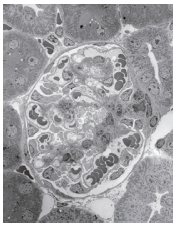

・腎臓糸球体の広視野観察(fig.2

腎臓は血液から尿を産生する臓器です。(fig.2)の中央に血液から尿をろ過する球状の糸球体があり、その周りにろ過液から必要な成分を再吸収する尿細管があります。